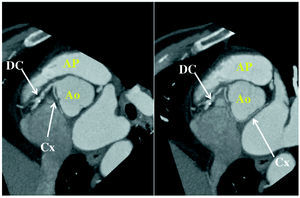

In patients with a poor echocardiographic window, or when diagnostic doubt persists despite the clinical indications, to enable the visualization of the origin and initial course of the CAA, transesophageal echocardiography (TEE),7,26,42,43 computed tomography (CT)26,44-46--with electron beam or multislice--(Figure 3) or cardiac magnetic resonance imaging (CMRI)26,47,48 can be performed (Figure 4).

Figure 3. Multidetector computed tomography image showing circumflex coronary artery (Cx) originating in right coronary artery (CD), following a retroaortic course to arrive at its normal distribution territory. Ao indicates aorta; AP, pulmonary artery. Courtesy of Dr. Gabriel C. Fernández, Servicio de Radiología, Hospital Povisa, Vigo, Spain.

2. Retroaortic, usually followed by the Cx with origin in right sinus of Valsalva or in right coronary artery, adjacent to posterior aortic wall, in the groove between the atrium and aorta (transverse sinus) (Figure 3).